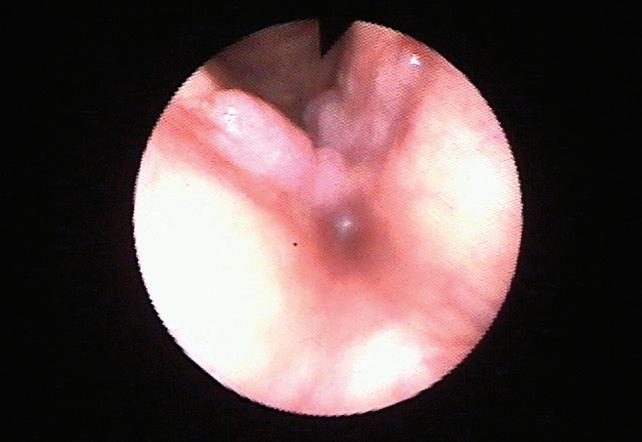

Протича с тежка оталгия, с кожни

12%

протича и със засягане на лицевия нерв, под името на Ramsay Hunt syndrome.

От прегледа се установява наличие на везикуларна еритема обикновено около ушната мида, външния слухов проход, конха. Обривът може да е разположен ретроаурикуларно по кожата, латералната назална страна и преднолатералната страна на езика.

Пахиеритема, съпроводена с уплътняване в засегнатите дерматоми, с регионална лимфоаденопатия. Групирани херпетиформени везикули, развити върху еритематозна основа, едностранно, лимитирани от края на засегнатите сензорните нерви. Вначалото везикулите са с бистро съдържимо, което впоследствие потъмнява, разкъсва се с последващи крусти. Може да се развие допълнителна вторична инфекция.Теси